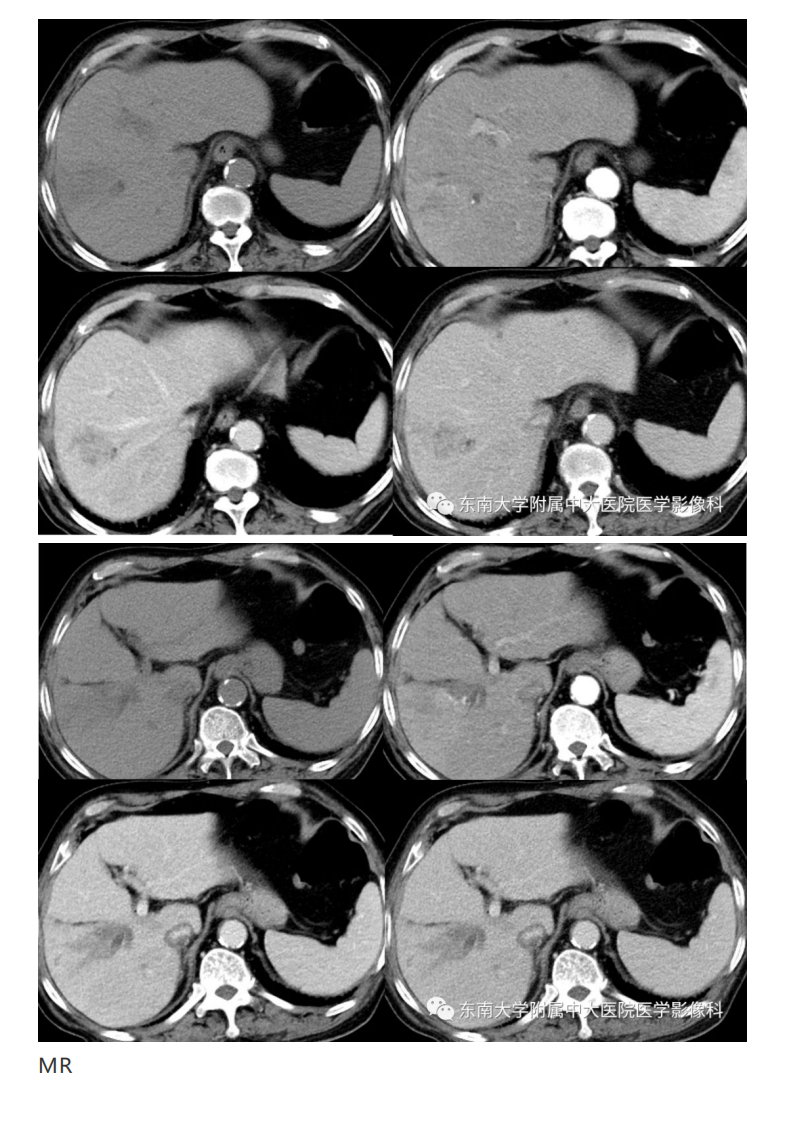

中大放射

20191230_2【晨读结果公布】2019.12.30消化系统疾病.pdf